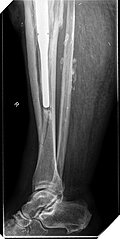

Im weiteren Verlauf zeigten sich die Weichteile des rechten Unterschenkels zunehmend mazeriert und belegt. Zudem sei der Patient erneut gestürzt. Eine erneut durchgeführte Röntgendiagnostik zeigte erneut eine periprothetische Tibiafraktur (Abbildung 3) bei einliegender achsgeführter KTP mit langem tibialem Stem und bekanntem periprothetischem Infekt mit Candida parapsilosis. Wir haben die Befunde ausführlich mit dem Patienten besprochen und in Zusammenschau der Befunde schließlich die Indikation zur Oberschenkelamputation gestellt.

Diese konnte komplikationslos im Mai 2018 durchgeführt werden (Abbildung 4 und 5).